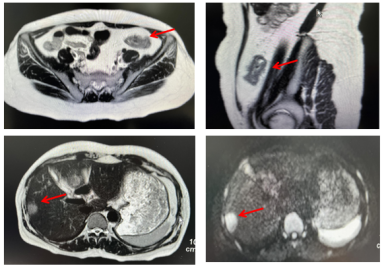

2023-08-25复查发现结直肠癌腹膜后淋巴结转移(术后6年)(1)CEA:26.70ng/mL。(2)2023-08-24胸部CT:肺转移瘤术后改变,右肺上叶术区斑片索条影同前;左肺、右肺中叶及下叶新增数个粟粒、微结节,建议密切随诊;(3)2023-08-25腹部MRI:乙状结肠癌根治术改变,吻合口区未见明显恶性征象;下腹部腹膜后至双侧髂血管起始段旁新增转移淋巴结,较大者36mm×22mm;右肝转移瘤切除+部分大网膜切除术后改变。(4)PET-CT未查。

image.png

图3 2023-08-25腹部MRI